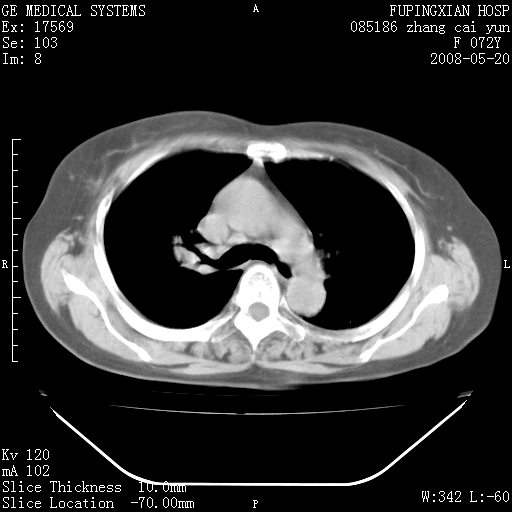

标题: CT13542:发热,咳嗽数日,经抗菌素治疗好转,请大家看排除 [打印本页]

标题: CT13542:发热,咳嗽数日,经抗菌素治疗好转,请大家看排除

右上叶支气管走行自然,未见明显管壁增厚等征像,另左主支气管起始部可见异常腔道向左侧延展左肺动脉干后方,与左下叶支气管相通,为左下叶支气管变异?

右肺上叶实变影,内见支气管充气征,右上叶支气管通畅,肺门区未见软组织密度影,抗炎治疗有效,考虑炎症,建议继续抗炎治疗复查。

右肺阻塞性肺炎  不除外支气管内膜结核

考虑为:右肺上叶感染性病变。建议:1)继续抗炎治疗后复查。2)必要时行纤支镜检查。

右上肺实变,间内有支气管充气征,考虑炎症,建议抗炎后复查